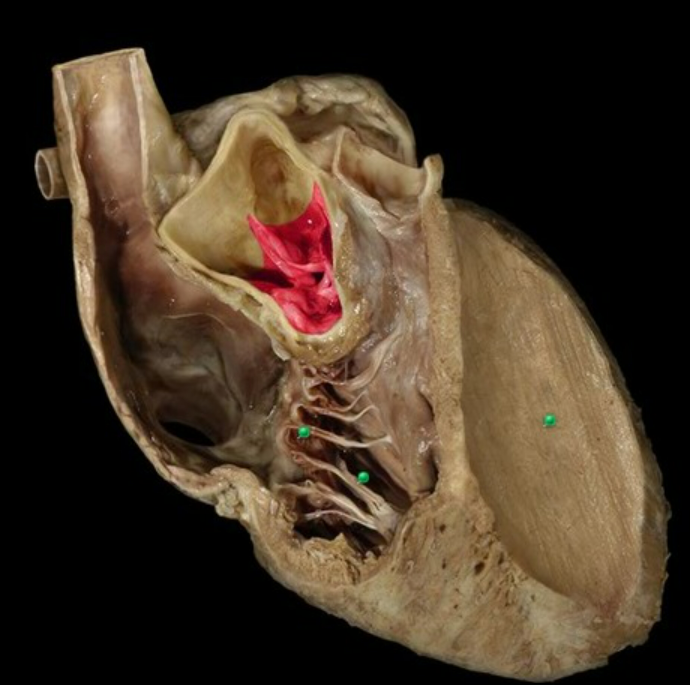

14

Q

A

Bicuspid / Mitral / Left Atrioventricular Valve

18

Name this structure and give the names of all the chambers of the heart that contain it.

Papillary Muscle

Right and Left Ventricles

19

Name this valve

Tricuspid / Right Atrioventricular Valve

20

Pulmonary Semilunar Valve

24

What is this structure and which kinds of valves possess them?

Chordae Tendineae of Valve

Atrioventricular Valves (Tricuspid and Bicuspid valves)